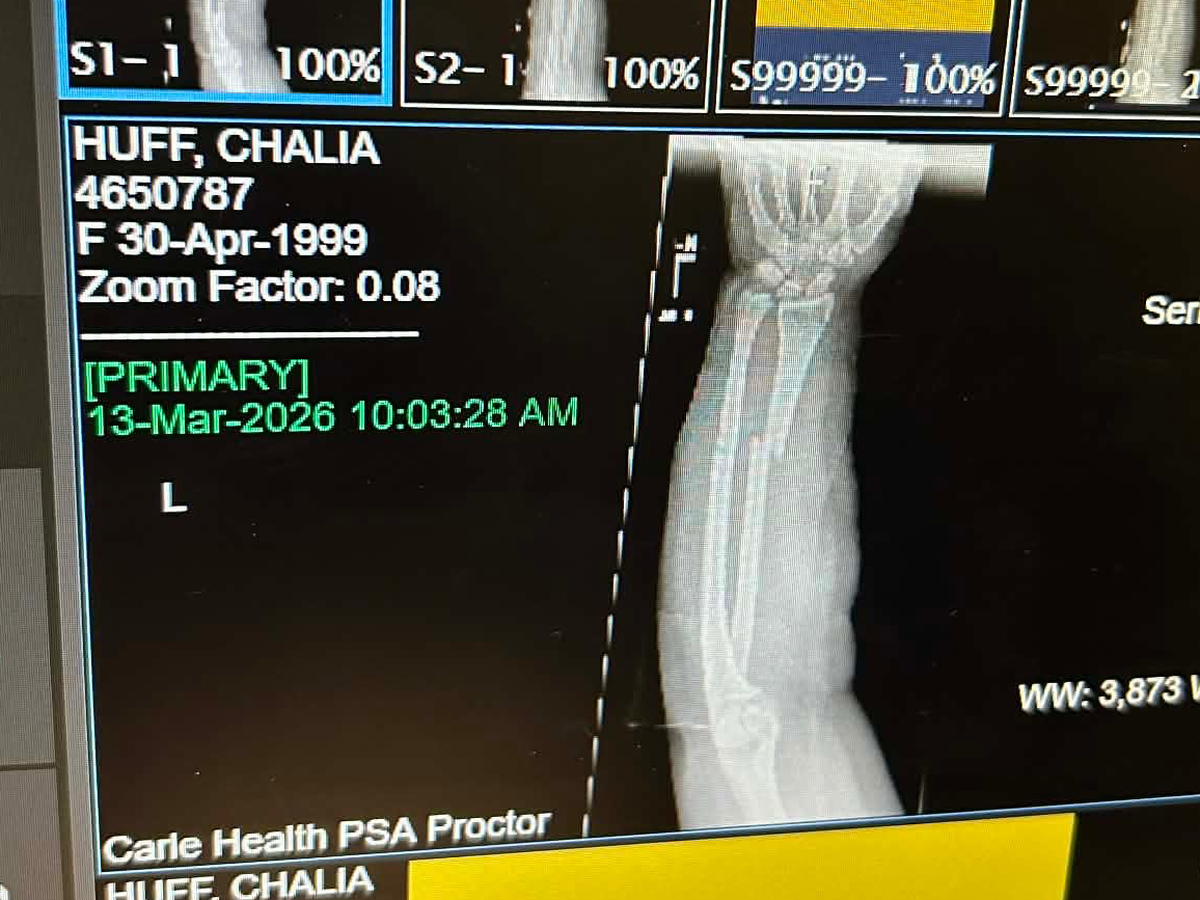

On Friday the 13th of March, I fell off of my electric bike trying to get to the bank. The fall resulted in me breaking both my radius and ulnar bones in my arm and fracturing my scaphoid bone in my wrist. During the time of my fall, I had no insurance and I’ve had to come out of pocket for my splint and sling costs, transportation to and from the doctor's offices and hospital, and overall having to overpay some not-so-good friends for help.